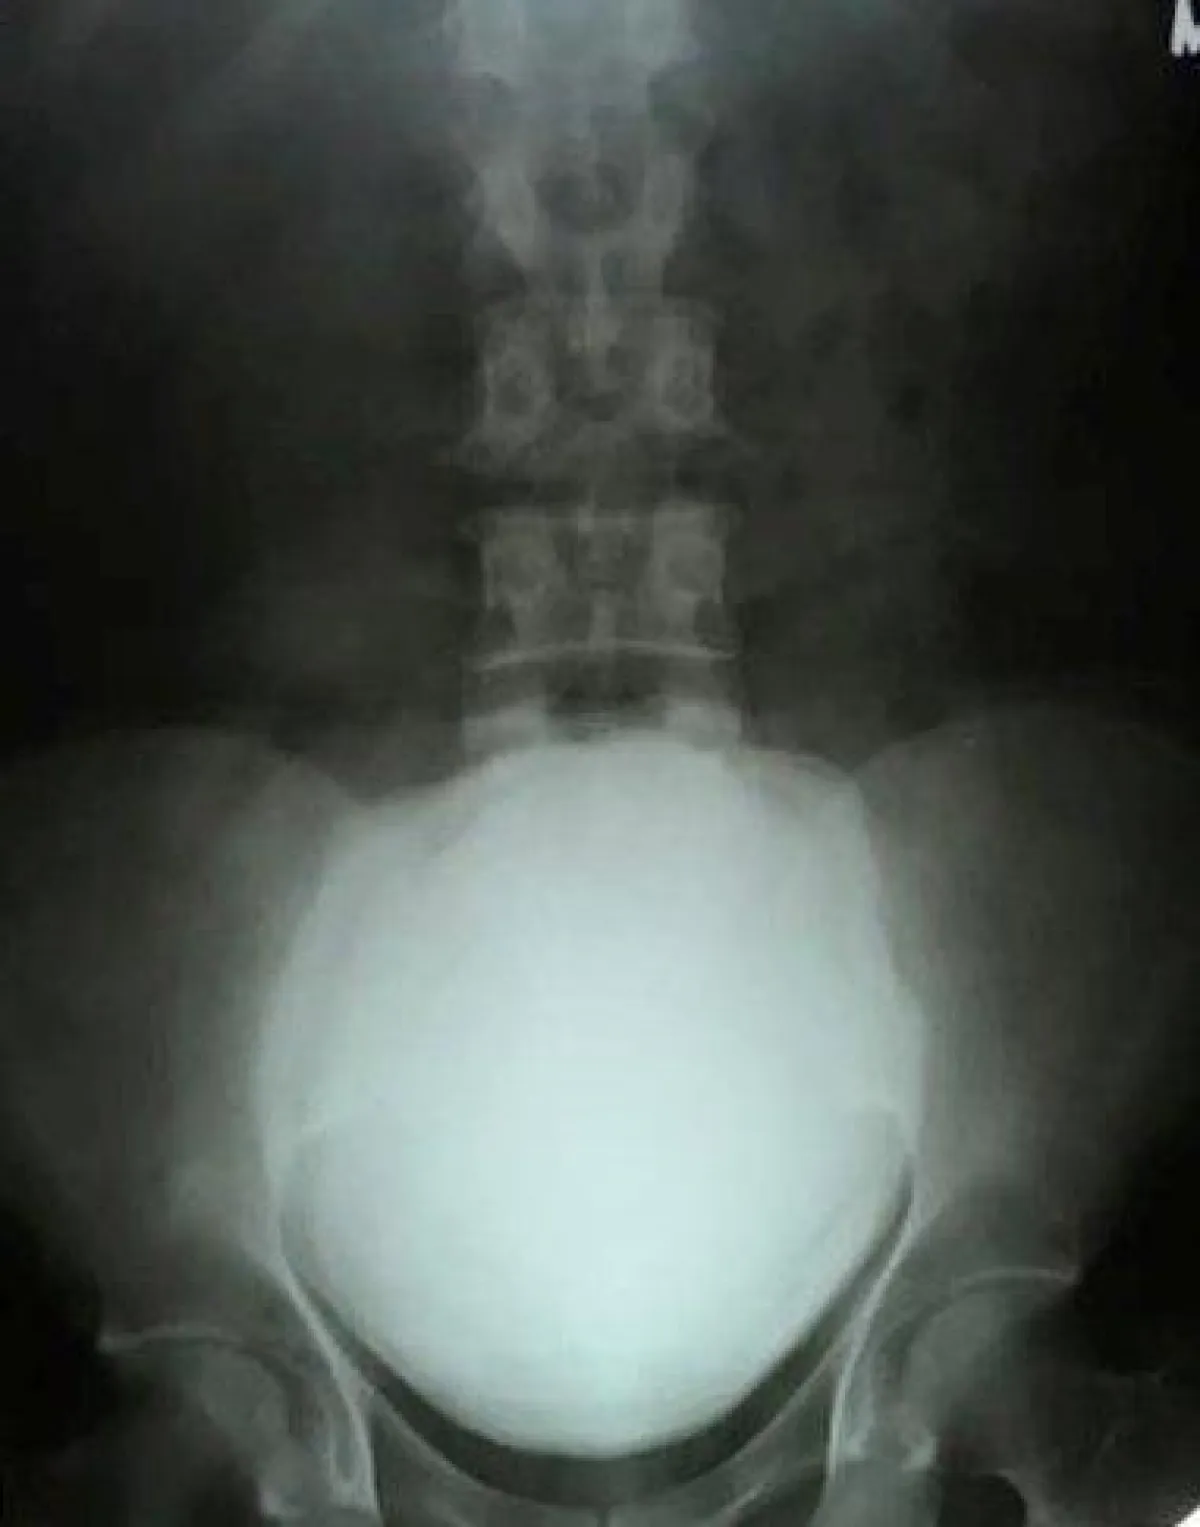

عانى رجل هندي من ألم مفاجئ في بطنه، فتوجه إلى المستشفى ليكتشف عن طريق الأشعة السينية، حجرا يبلغ طوله 11.5 سم وعرضه 17 سم ووزنه 3 باوند، ما يعادل نحو 1.36 كلغ، داخل مثانته.

وقد خضع ماهيش باتيل، البالغ من العمر 49 عاماً، لعملية جراحية لاستخراج الحجر المتكوّن من الكالسيوم داخل مثانته.